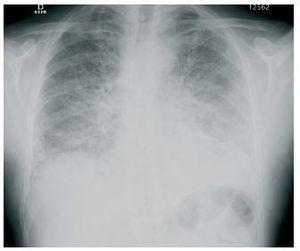

Los hallazgos de laboratorio mostraban 3.980 leucocitos/μl (eosinófilos 29,3%), hemoglobina 12,1 g/dl, plaquetas 276.000, creatinina 1,79 mg/dl, sodio plasmático 138 mEq/l, potasio plasmático 3,9 mE/l, y niveles plasmáticos de everolimus de 14 ng/ml. En la radiografía de tórax se observó un patrón intersticial bilateral, y en la TAC torácica, infiltrados y nódulos pulmonares con engrosamiento del intersticio bilateral (figura 1 y figura 2). La antigenemia y cultivo de citomegalovirus (CMV) fueron negativos, así como el antígeno de neumococo y Legionella. Se realizó broncoscopia con signos de broncopatía crónica, con resultados de BAL y BAS negativos. Se inició tratamiento empírico de amplio espectro antibiótico y antiviral, sin mejoria clínica y con empeoramiento radiológico, por lo que, con sospecha de neumonitis por everolimus, se decidió la retirada de este fármaco y la introducción de tacrolimus. El día posterior a la retirada de everolimus el paciente presenta mejorías clínica y radiológica progresivas con resolución del cuadro.

Figura 1. Radiografía de tórax